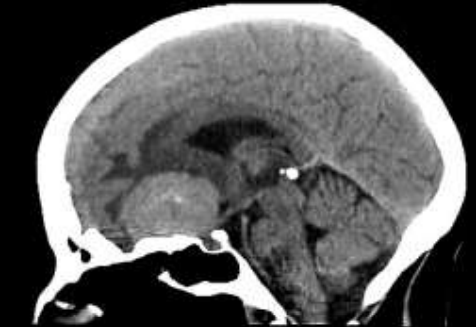

Assinale a alternativa que descreve corretamente o sinal radiológico abaixo e o possível diagnóstico a ele associado.

Enunciado 3028041-1